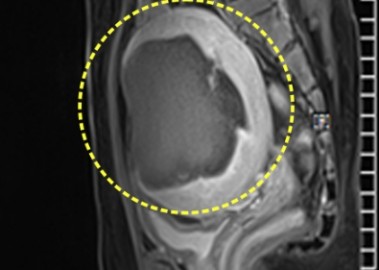

장막하근종 치료 사례